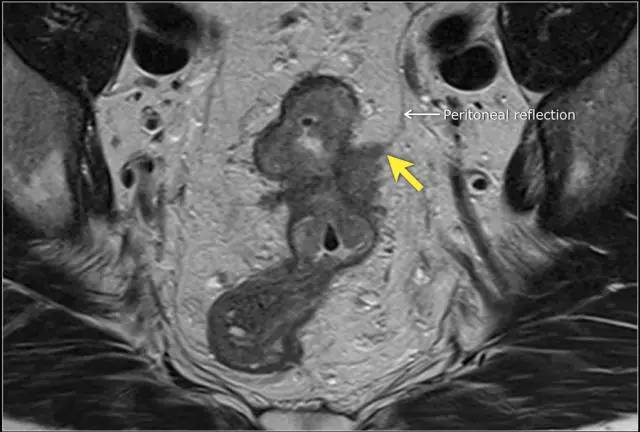

T4a 分期,侵出腹膜反折

低直肠完全被直肠内筋膜覆盖。在直肠中部,其后侧和外侧由直肠内筋膜覆盖,但在前侧由内脏腹膜覆盖。内脏腹膜生长意味着扩散到腹膜腔。在矢状 T2 加权图像上,腹膜反折可以描绘为连接膀胱与直肠前后方面的低信号细线。

图 14 轴向 T2 加权图像上,沿着内脏腹膜有肿瘤向内生长(箭头)

图 15 同一患者腹膜转移的矢状图(箭头),在直肠内还有可疑的淋巴结